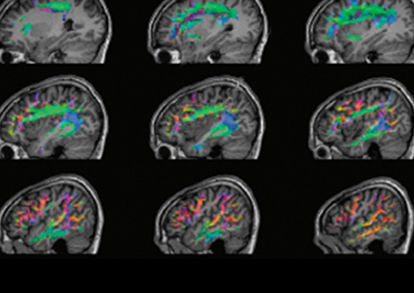

From form to function, SIGNA™ Premier powers neuroscience research and discovery

UCLouvain and the University of Copenhagen detail their use of the SIGNA™ Premier 3.0T system in fMRI studies of neurodegenerative, psychiatric diseases as well as developmental disorders.